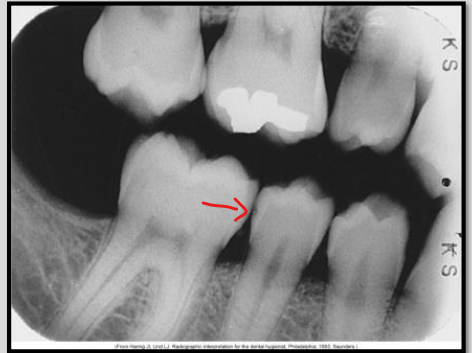

Identify the carious lesion.Â

Root surface cariesÂ